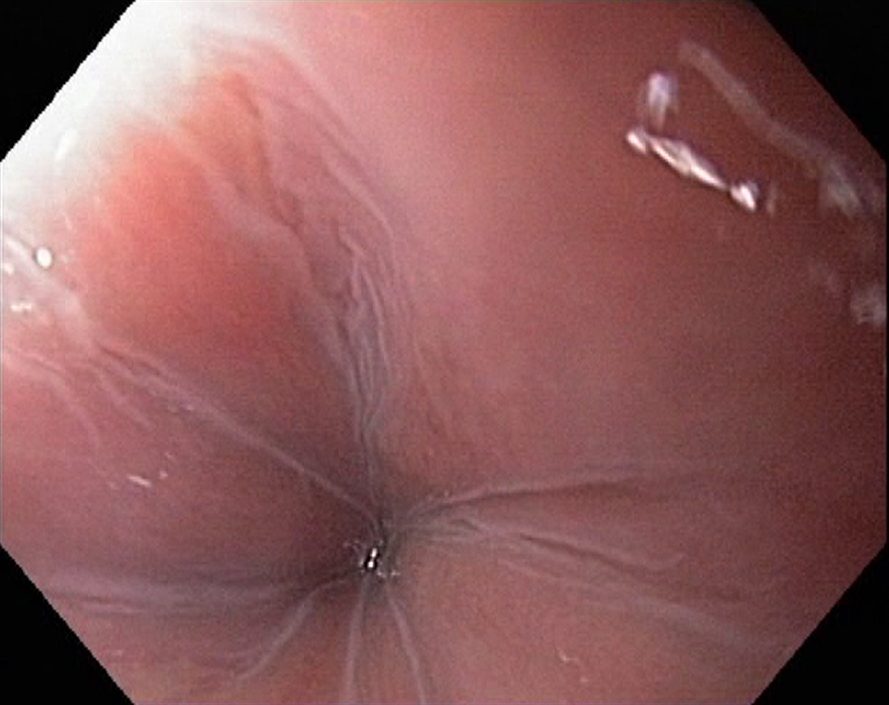

Achalasia cardiae is a motility disorder of the oesophagus, where there is a nerve degeneration in the Auerbach´s plexus, causing inability of the lower oesophageal sphincter in the cardia region (C) to relax. In oesophageal x-ray examanations a dilatation of the oesophagus is seen, and the contrast stays in the oesophagus for a long time. Endoscopy shows a quite normal cardia, and in less severe cases the endoscopic diagnose is not easy. Dysphagia is the main symptom, causing weight loss in severe cases. Achalasia can be treated with medicines (nifedipine, nitrates), botulinumtoxin injections in the cardia, dilatation during endoscopy and surgically (Heller´s myotomy).